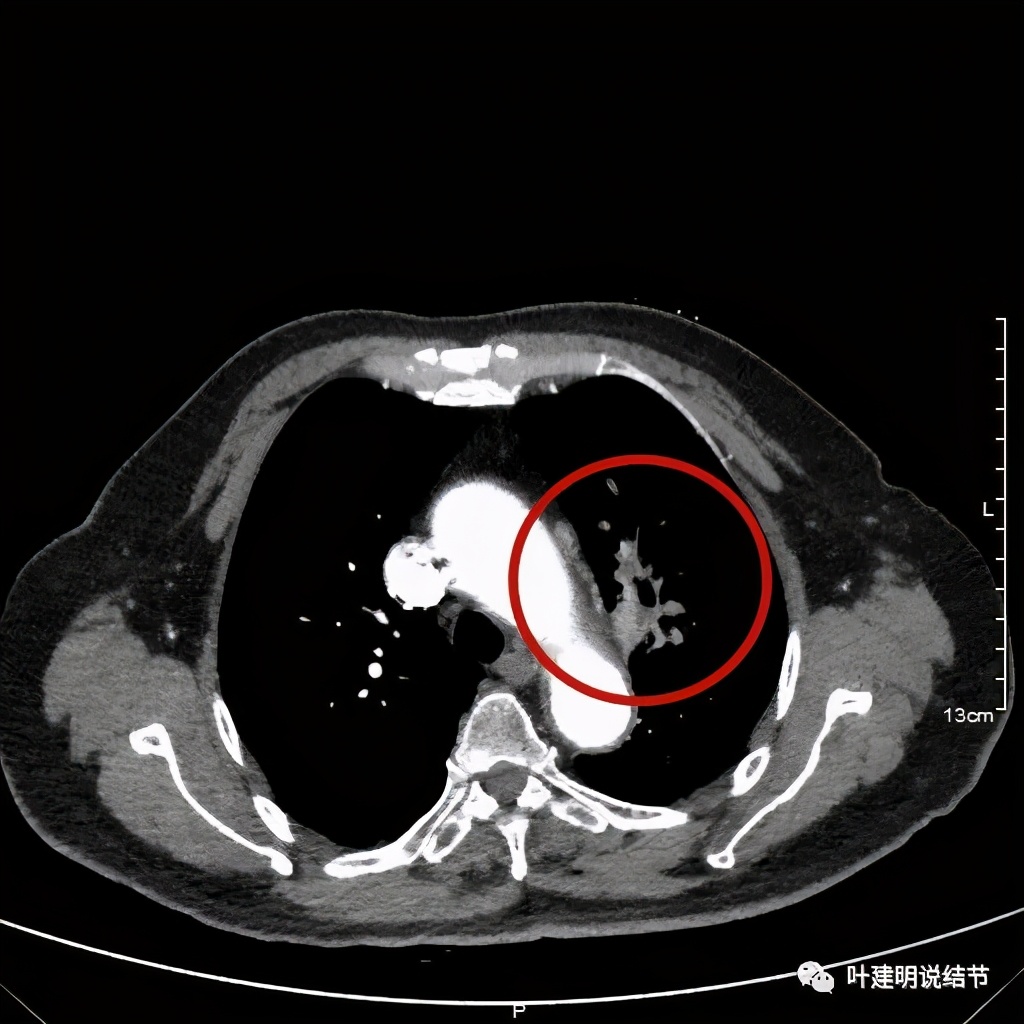

上图示肿瘤部位仍与肺动脉关系密切,似乎未能脱开,红色示肿瘤处